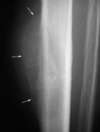

Ostéome ostéoide fémoral

Ostéome ostéoïde

nidus calcifié au sein de l’importante réaction périostée. Notez les fines stries radiaires partant du nidus, compatibles avec de fines artérioles.